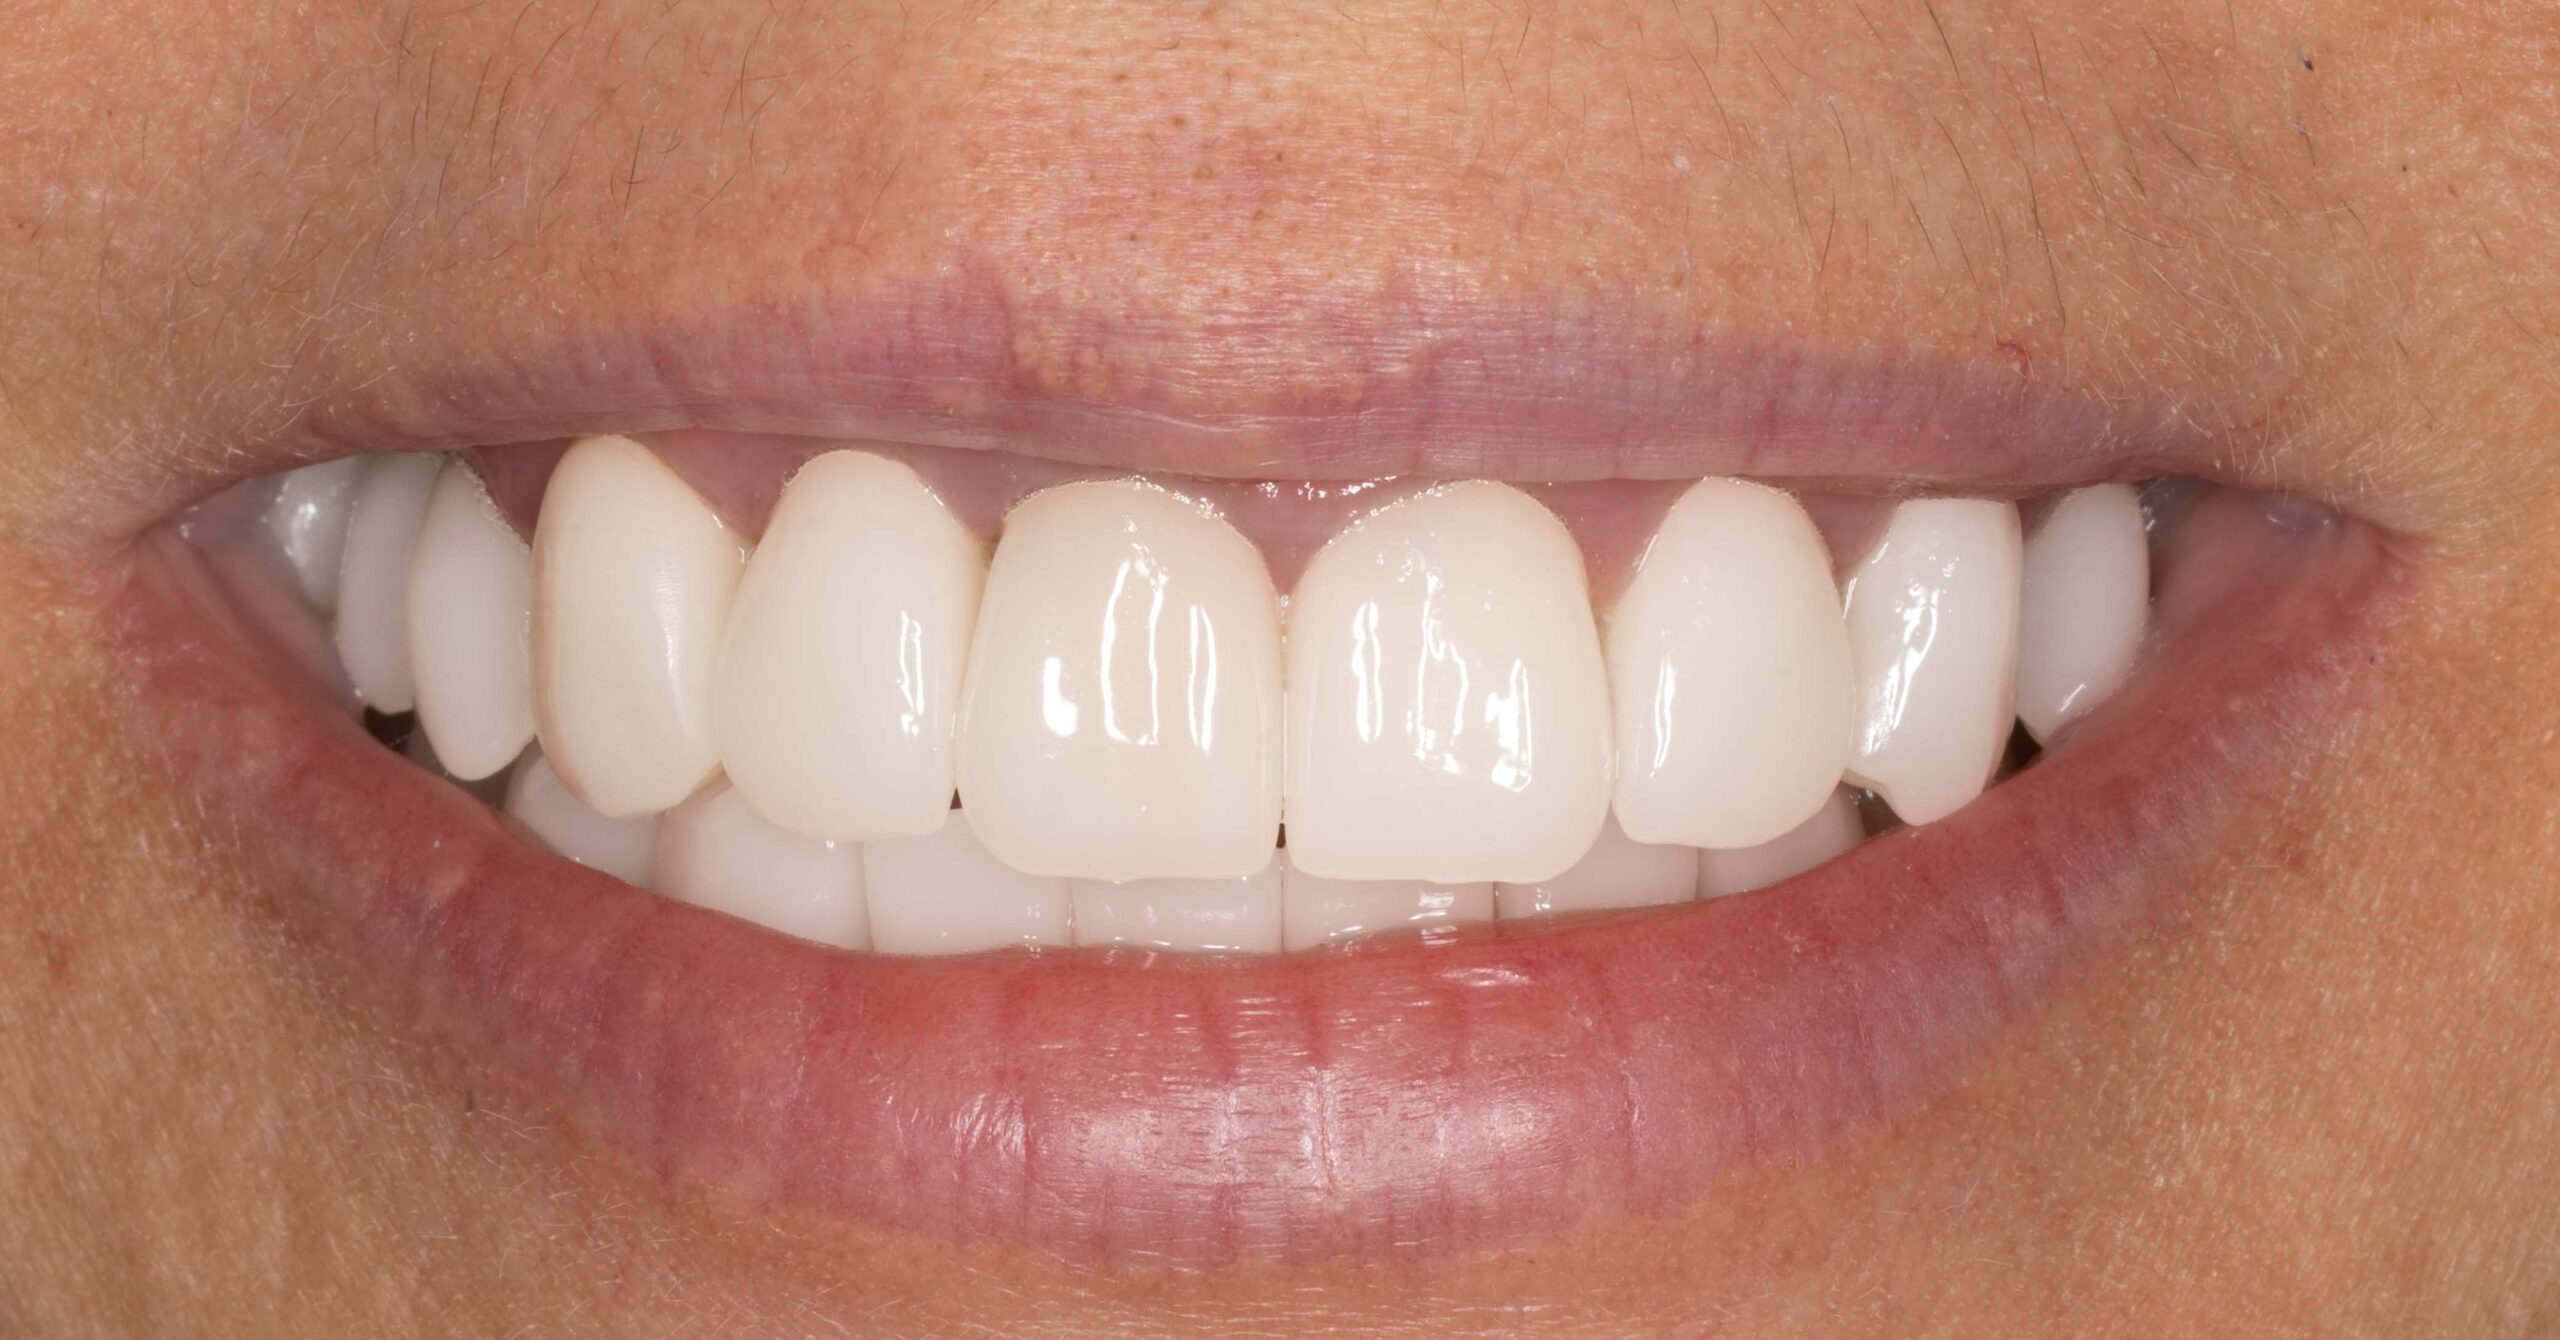

utrata zęba po urazie

Nasi pacjenci mogą liczyć na niezwłoczną oraz profesjonalna pomoc w każdej, nawet najbardziej stresującej sytuacji. Młoda pacjentka zgłosiła się z powodu utraty zębów przednich, do czego doszło kilka dni wcześnej, w wyniku potracenia przez kierowce elektrycznej hulajnogi. Leczenie polegato na niezwtocznym wprowadzeniu implantów zebowych oraz tymczasowej odbudowie zebów, dzieki czemu pacjentka jeszcze tego samego dnia odzyskata peten usmiech. Wprowadzenie implantów w odcinku przednim stanowi niezwykte wyzwanie. Aby osiagnac naturalny wyglad oraz wysoka estetyke czesto wymaga dodatkowych zabiegów regeneracyjnych na okolicznych tkankach miekkich oraz twardych. Przedstawiony efekt to uśmiech po wykonaniu ostatecznej odbudowy protetycznej.